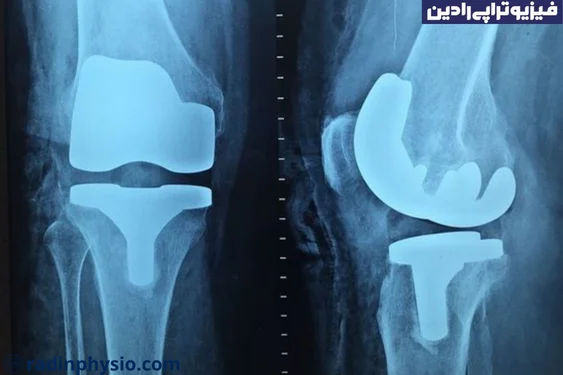

جراحات ارتوپدی

در برخی جراحات ارتوپدی مانند تعویض مفصل، تعویض استخوان، کورکتور بزرگسالان و فیوژن استخوانی، نیاز به پیوند استخوان ممکن است وجود داشته باشد. این عمل به کمک تثبیت استخوانی و تسهیل فرآیند بهبودی کمک میکند.

در برخی موارد، عملیاتهای ترمیمی استخوان ممکن است نیاز به استفاده از گرافت استخوانی داشته باشند. این عملیاتها ممکن است شامل تعویض مفصل، ترمیم استخوان پس از استئوپروزتیک (جایگزینی مفصل به شکل کامل یا جزئی)، ترمیم استخوان پس از جراحی ترمیمی غیرموفق یا استفاده از گرافت استخوانی در ترمیم ترکها یا نقصهای هسته استخوانی میشود.